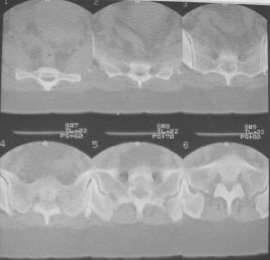

Из анамнеза: в ноябре 2002г. оступилась,упалана трап самолета (на верхней площадке, сразу при выходе из салона) на правый тазобедренный сустав, а затем - вниз на землю на ноги и ягодицы. Потеряла сознание от боли. Доставлена в больницу по месту жительства, лечилась консервативно с диагнозом кокцигодиния.На рентгенограмме от 27.11.02г. вывиха копчика не определяется (снимок идентичен представленной R-грамме от28.11.03г., кроме этого есть нормальная R-грамма копчика в боковой проекции).Через три недели стала ходить, но привести правую ногу в тазобедренном суставе не могла. Сейчас ходит отведя кнаружи правое бедро и голень, как ножку циркуля (фото 1). Неврологических нарушений нет. По просьбе врачаможет на 30-40 секунд поставить ноги вместе (фото 2). При этом испытывает сильную тянущую боль и ощущение "вывернутости" в правом тазобедренном суставе. Эти ощущения заставляют вновь отвести бедро. В положении лежа разогнуть бедро полностью не может из-за болей в ягодичной мышце (фото 3). Сгибание также ограничено из-за болей (фото 4). Отведение в положении лежа возможно в том же объеме, что и стоя (фото 5). Заподозрен старый разрыв правого крестцово-подвздошного сочленения.Выполнено R-исследование и КТ(в приложении). По-поводу деформации лонного сочленения выяснен гинекологический анамнез. Роды одни, нормальные в 22 года. Из роддома выписана на 8 сутки, нарушения походки не было, R-графия таза не проводилась. Вопросы на обсуждение: 1. Диагноз либо алгоритм дальнейшего обследования. 2. Лечебная тактика (в первую очередь возможность и целесообразность оперативного лечения).

Отсутствие изменений сустава на КТ и обычных рентгенограммах, стойкие боли и ограничение подвижности в суставе - симптомы, характерные для повреждения ацетабулярной губы. ЯМР с контрастом или без должны прояснить картину.

Уважаемый Юрий Алексеевич, сделаны ли пациентке более дистальные срезы КТ с захватом области тазобедренного сустава? Учитывая давность травмы, могли присоединиться и дистрофические процессы в субхондральной кости головки и впадины. Изменения в капсуле будут хорошо видны на УЗИ, особенно в сравнении со здоровой стороной. Эффективность лечебно-диагностического введения гормональных препаратов, на мой взгляд, сомнительна ввиду давности патологического состояния. При такой стойкой и давней контрактуре без операции вряд ли можно обойтись. Под наркозом амплитуда на разгибание должна увеличиться, усилить эффект можно тено-миотомиями заинтересованных групп мышц, капсулотомией + в послеоперационном периоде хорошее консервативное противовоспатлительное лечение с укладками на разгибание.Что мешает приведению пока не ясно, во встретившихся в нашей работе аналогичных ситуациях причиной был формирующийся медиальный остеофит головки, выталкивающий её из впадины.